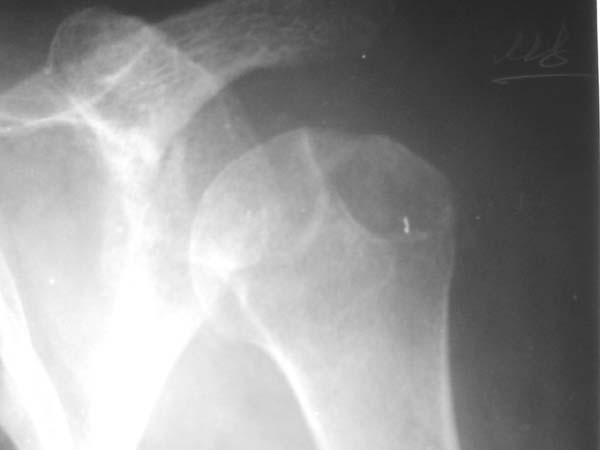

Уважаемые коллеги!Женщина, 60 лет. 3 недели назад упала с упором на отведенную левую руку. Почувствовала боль в левом плечевом суставе. За помощью не обращалась. 2 недели "мази и припарки". Затем - рентгенограмма (r1 и r2), жалобы на боли,ограничение движений...

Активное отведение 80 гр., при пальпации - головка плечевой кости безболезненно вправляется и тут же самостоятельно вывихивается. Наложена косыночная иммобилизация, рентгенография (r3) и МРТ.В нашем диагностическом центре МРТ исследование плечевого сустава выполнено впервые, опыта у нас маловато :(.Вопросы: уточнение диагноза? какие исследования провести? тактика лечения?

Как Вам известно, в некоторых случаях вывихи плеча сопровождаются разрывом ротаторной манжетки, отрывному перелому большого бугорка что приводит к потере наружной ротации и отведения плеча. На представленных рентгенограммах перелом не виден.

МРТ должен показать разрыв манжетки, но признаться я не большой эксперт по чтению МРТ сканов, хотя затемнение, отек мягких тканей по задней поверхности плеча видны Обычные рентгенограммы демонстрируют остеолизис в области большого бугорка.

1. На рентгене - нижний подвывих плеча и очаг остеолиза суставного бугорка с четкими контурами (вдавленный перелом на фоне остеопороза ? доброкачественная опухоль? аваскулярный некроз ? (хотя ни разу не слышал об аваскулярном некрозе плеча..)

Судя по снимкам, речь идTт о типичном случае Hill-Sachs Lesion. По этому поводу я позволю себе некоторый экскурс:

97 % всех вывихов плеча происходит по механизму комбинации отведения, разгибания и наружной ротации (А. Гринспан). В момент вывиха головка плеча ударяет о нижний край гленоида, что ведет к вдавленному или компрессионному перелому одной или обеих структур. Чаще всего, однако, повреждение возникает в задней латеральной области головки плечевой кости на переходе от головки к шейке. Этот диагноз можно выставить на основании рентгеновского снимка в переднезадней проекции с внутренней ротацией плеча. Несколько реже видно повреждение гленоида о передненижний перелом края. То, что мы называем Bankart Lesion. Это повреждение видно на ре. снимке в п.з. проекции при нейтральной позиции плеча. Разумеется хрящевые и мягкотканные повреждения (в смысле Банкарт) мы увидим лучше всего на ЯМР.